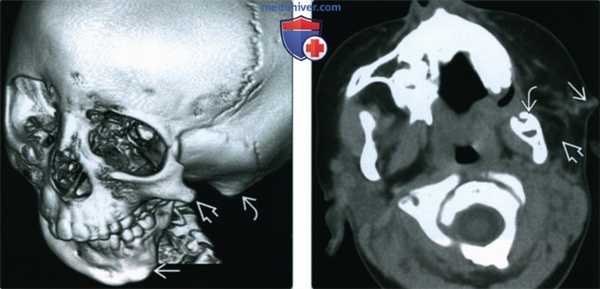

(Слева) На 3D КТ у семилетней девочки с гемифациальной микросомией (ГФМ) определяется уменьшение нижней челюсти слева, гипоплазия скуловой дуги, недоразвитие сосцевидного отростка и атрезия наружною слуховою канала.

(Справа) При аксиальной КТ без КУ у четырехлетней девочки с ГФМ определяется уменьшение дуги нижней челюсти слева, визуализируется преаурикулярный свищевой ход, а также «метка» на коже. Жевательные мышцы слева недоразвиты; жевательная мышца и околоушная железа не визуализируются в ожидаемом месте.

2. КТ при гемифациальной микроскомии:

• КТ в костном окне:

о Микрогнатия:

- Обычно односторонняя, реже двухсторонняя или асимметричная; гипо- или аплазия ВНЧС

о Гипоплазия/отсутствие скуловой дуги

о Гипоплазия жевательных мышц и мышц лица

о Гипо-/аплазия околоушной железы ± добавочная околоушная железа

о Височные кости: врожденные аномалии наружного и среднего уха (СЕМЕМ):

- НСК: стеноз/атрезия, уменьшение/отсутствие тимпанической пластинки

- Сосцевидный отросток: ± вариабельное снижение пневматизации

- Пространство среднего уха: вариабельная гипоплазия

- Слуховые косточки: мальформация, ротация, слияние

- Овальное окно: ± стеноз или атрезия

- Канал ЧН VII (КЛН): норма или гипоплазия:

Тимпанический КЛН±расхождение/абберация

Сосцевидный КЛН вентральнее, иногда в ВНЧС

- Внутренне ухо: случайные мальформации

о Лицо: ± расщелины лица; ± других структур, например, глазниц

о Позвоночник: + аномалии слияния/сегментации